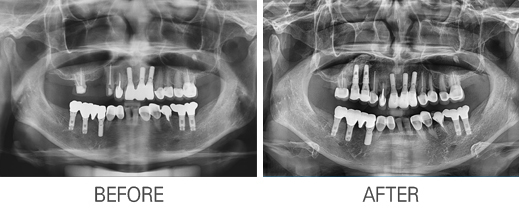

Àüü ÀÓÇöõÆ®

»ÀÀÌ½Ä ÀÓÇöõÆ®

±³Á¤À» µ¿¹ÝÇÑ ÀÓÇöõÆ®

Ä¡Á¶°ñÀÌ½Ä ÀÓÇöõÆ®